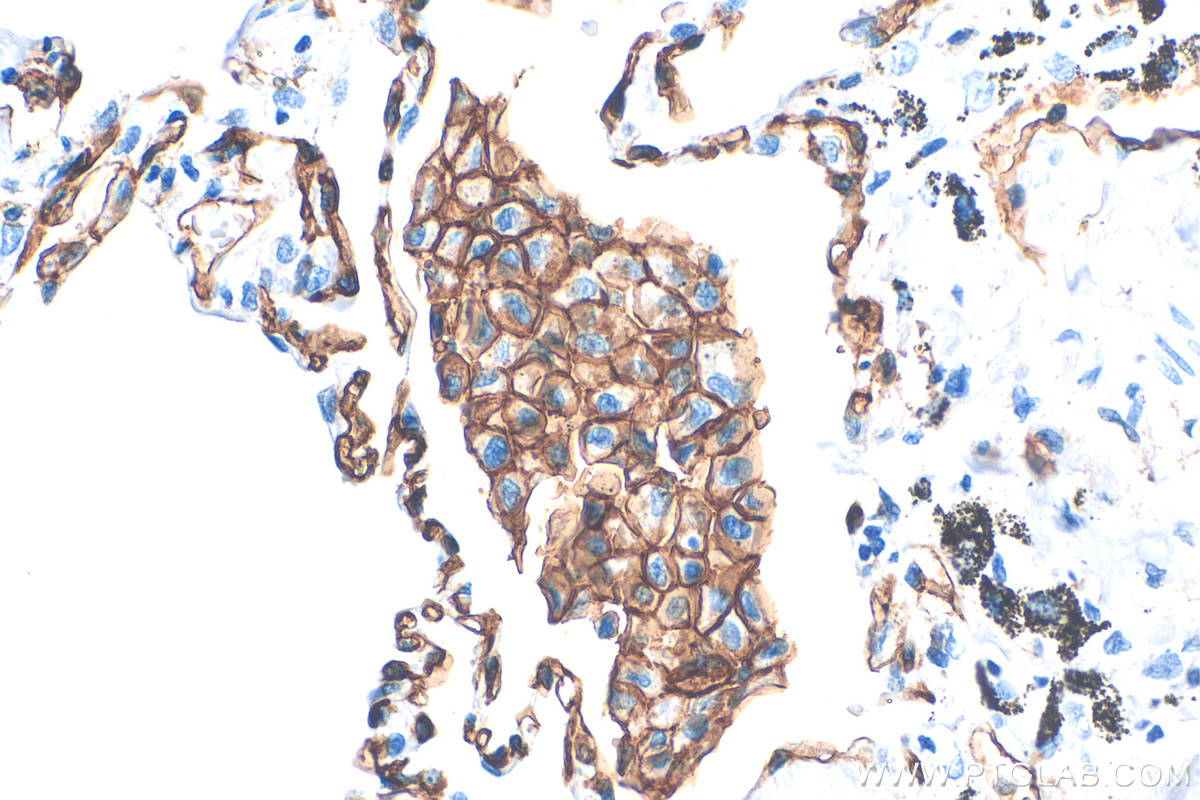

| Positive IHC detected in | human lung tissue, human cervical squamous cancer tissue, human lung squamous cell carcinoma tissue, human placenta tissue Note: suggested antigen retrieval with TE buffer pH 9.0; (*) Alternatively, antigen retrieval may be performed with citrate buffer pH 6.0 |

Thrombomodulin, also known as CD141, is an endothelial cell surface glycoprotein that forms a 1:1 complex with the coagulation factor thrombin and plays an important role as a natural anticoagulant. Thrombomodulin serves to convert thrombin from a procoagulant protein into the activator for protein C. Once converted to activated protein C (APC), this protein serves as a major anticoagulant in blood (PMID: 2827310). Thrombomodulin is also located in other cells (keratinocytes, osteoblasts, macrophages,...) where it might be involved in cell differentiation or in inflammation (PMID: 9814688). In humans, thrombomodulin is encoded by the THBD gene. Mutations in this gene are a cause of thromboembolic disease, also known as inherited thrombophilia. Thrombomodulin is glycosylated and has an apparent molecular weight of 75 to 110 kDa (PMID: 1650405; 2827310).